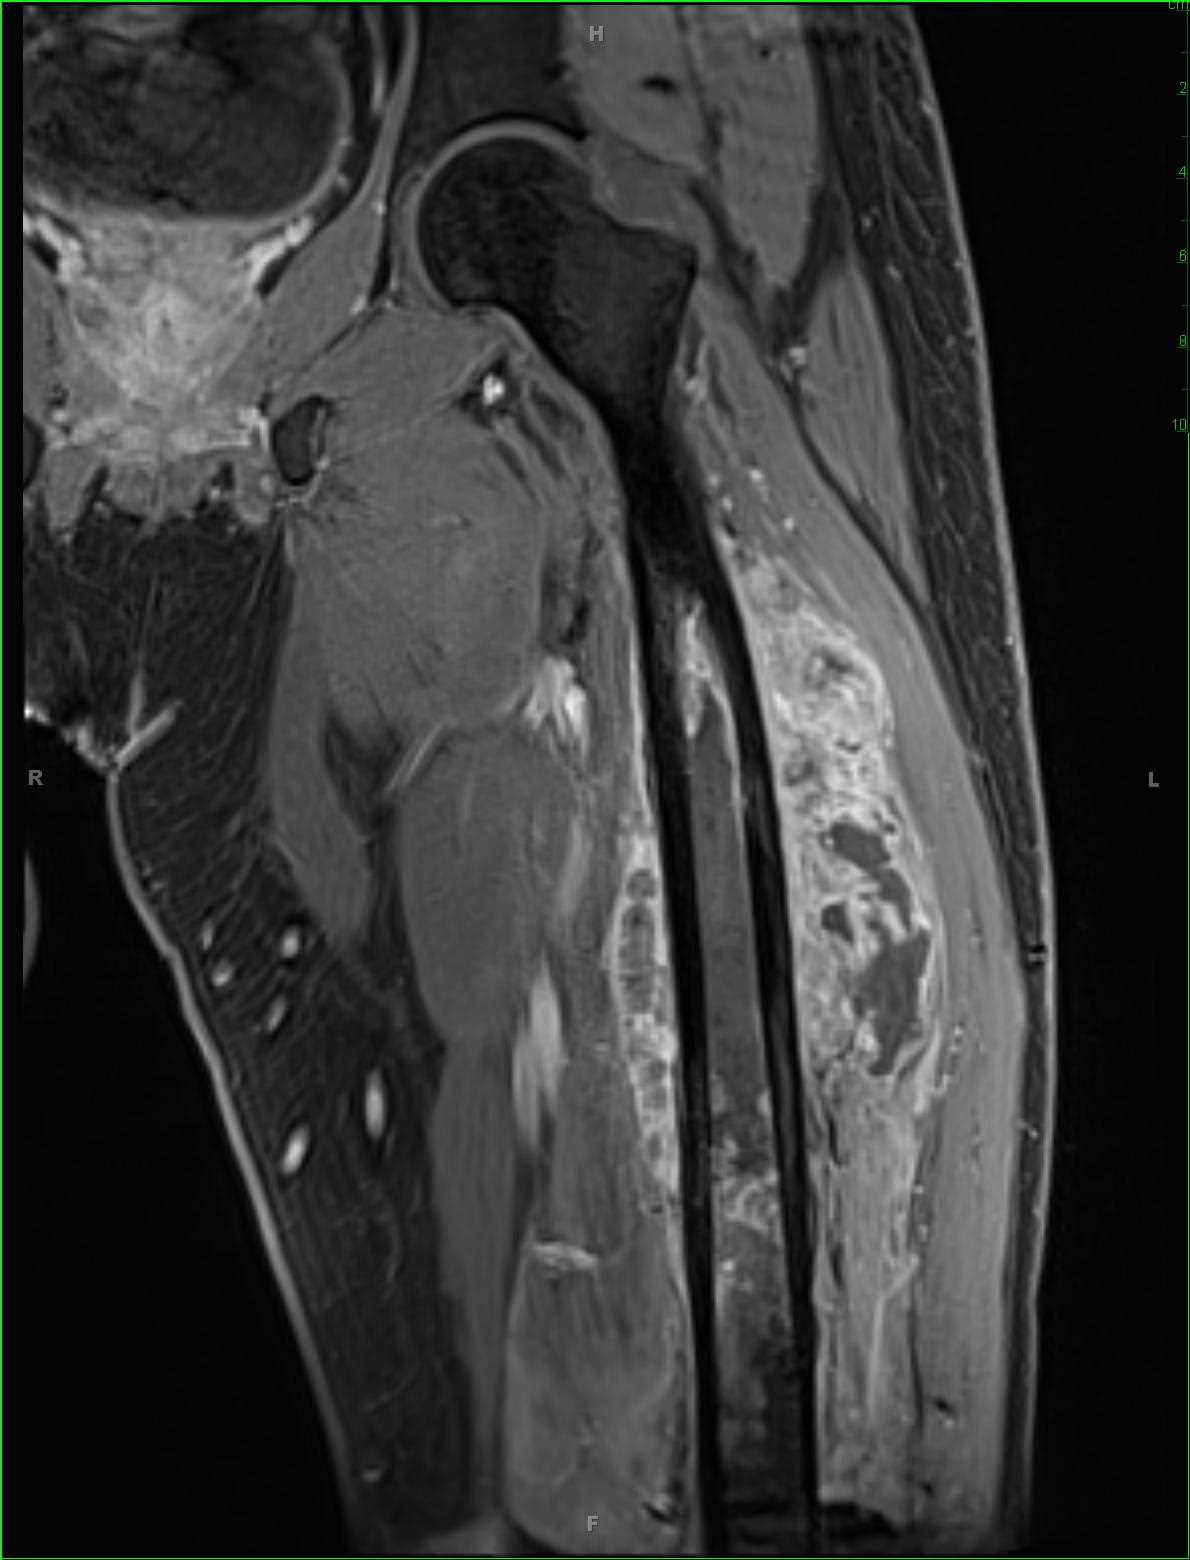

5.2 RM (imprescindible)

- 🔹 Elección para estadificación local: extensión intramedular, partes blandas, paquete neurovascular, articulación.

- 🔹 Recomendable RM de todo el hueso afecto (buscar “skip lesions” en el mismo hueso).

- ✅ Imagen clave: Rx con lesión agresiva permeativa y reacción perióstica laminar; RM para extensión local. TC torácico siempre. PET-TC muy útil para metástasis óseas y respuesta.